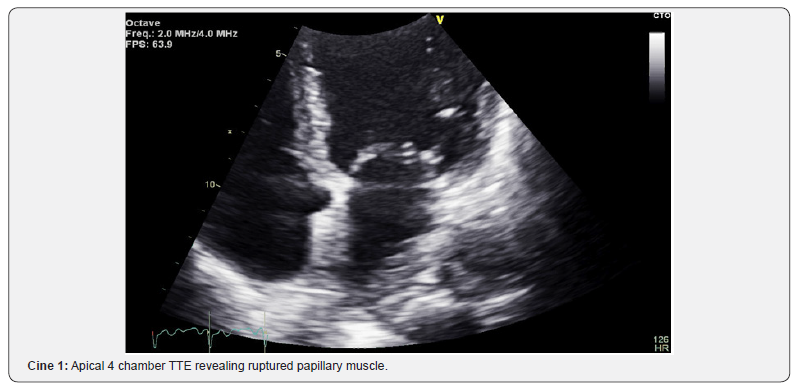

The echocardiographer went immediately to the emergency room as the catheterization laboratory prepared for the patient’s transition to the catheterization lab. The echo was performed to evaluate for wall motion, heart function, and the potential of mechanical complications. This examination can be performed in 5 minutes. The examination revealed an inferolateral wall infarct with a mechanical complication of papillary muscle rupture and severe mitral regurgitation (Figure 2) (Cine 1).